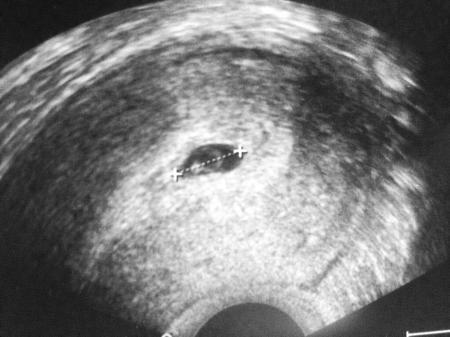

Toll das freut mich für dich. Ich hatt heut früh auch meinen 1. Termin. Bin auch so doll glücklich! Ich bin 6+2 und mei Krümelchen ist 5,3mm mit ner fruchthöhle von 1,5cm :)